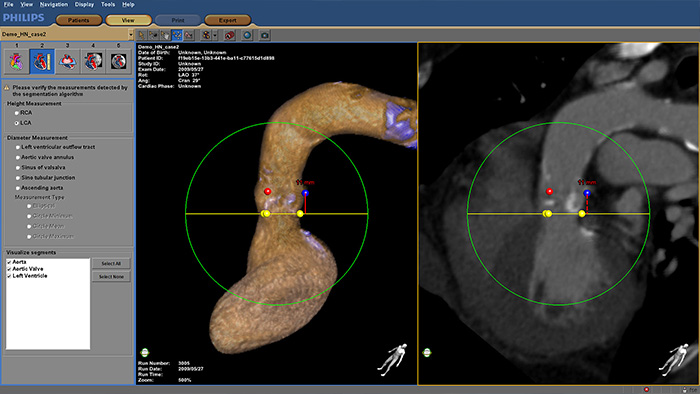

Increase confidence and ease during transcatheter aortic valve replacement (TAVR) and other challenging SHD procedures. The immersive user experience is highly automated to simplify planning, device selection and projection angle selection. During procedures, it provides live image guidance to support device positioning.